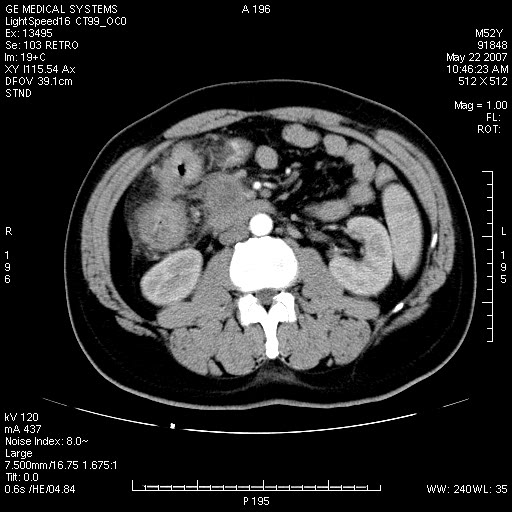

以下是引用余辉在2007-5-22 20:12:00的发言:[br]升结肠管壁明显增厚,增强有静脉期持续增强,结合患者病史,考虑结肠癌可能性大,临近脂肪影密度增高,混浊,恐有肠系膜浸润转移,建议镜检

以下是引用dyqct在2007-5-22 20:43:00的发言:[br]支持结肠肝曲占位性病变(浸润型结肠癌可能性大)。胆总管下端扩张,原因待查。

以下是引用gaoxiao在2007-5-22 20:49:00的发言:[br]考虑升结肠癌向周围侵犯,胰头钩突受侵。